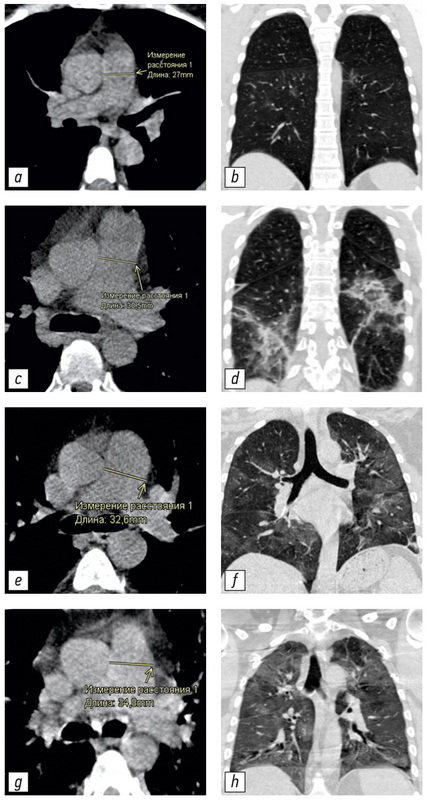

不同体积肺实质病变患者的CT图像及相应的肺动脉测量值在图3提出。

图 3 具有不同 PA 直径和肺部受累程度的 CT 图像示例:a、b - 未扩张的 PA(27.0 毫米),CT-1 肺部受累程度(小于 25%); c, d - 肺损伤程度 CT-2 (25-50%) 增大的 PA (30.5 毫米); e, f - 扩张的 PA (32.6毫米),肺损伤程度为 KT-3 (50–75%); g, h - 肺损伤程度 CT-4(大于 75%)的扩张 PA(34.8毫米)。 CT - 计算机断层扫描; CT 1-4 - 用于视觉评估患者全身状况严重程度对 COVID-19 肺部变化的放射学迹象的性质和严重程度的依赖性的改编量表; PA-肺动脉。